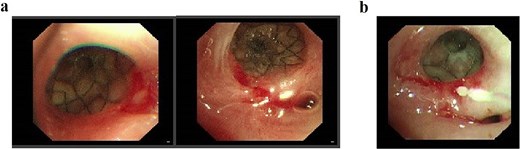

Following successful control of the pulmonary infection with conservative therapy, two bronchial stents were placed via fiberoptic bronchoscopy in the right mainstem bronchus to isolate the fistulous tract and prevent recurrent infection. Follow-up bronchoscopy after 2 weeks confirmed complete closure of the tract (Fig. 4), with resolution of infection markers and normalization of laboratory parameters. Fasting and gastric decompression were maintained to facilitate pleural tissue repair. After observing adequate thickening of the visceral pleura, oral intake was cautiously reintroduced, progressing from liquids to semisolid foods over 3 months. The patient tolerated this transition without infection recurrence, with sustained normalization of clinical and laboratory findings.

(a) Status following bronchoscopic stent placement. (b) Follow-up bronchoscopy demonstrating healed fistulous tract 2 weeks postintervention.